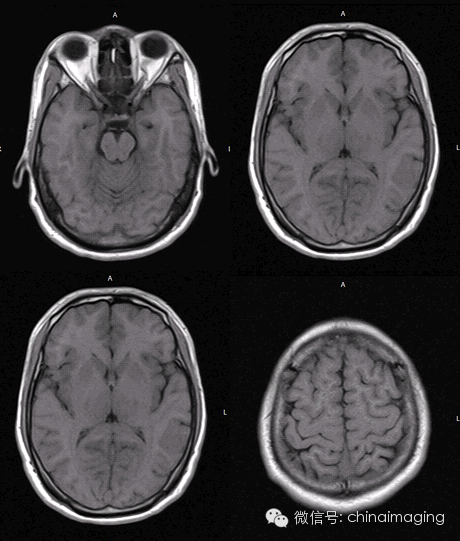

28岁男性,头痛、头晕、恶心、呕吐半天余,近期有感冒病史。

脑静脉窦血栓

1.CT 窦腔内圆形、椭圆形、三角形高密度影,1周后低密度改变。(1)空“△”症 出现率35-75%。(2)条索症 出现率<20%。

2.MRI 初期:正常、血管流空现象消失。继之:T1、T2像均为高信号。随血管再生:出现正常流空信号。